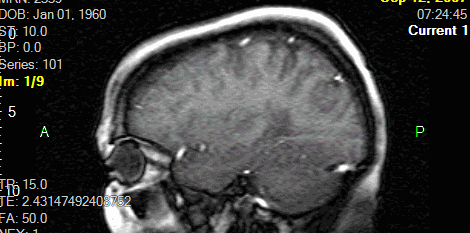

A csigolyaszámoló kurzorral címkézheti a csigolyákat és a csigolyaközöket. Ezek az előre meghatározott címkék saját megfelelő helyükön jelennek meg a képeken minden ortogonális síkban.

Csigolyaszámolás beillesztéséhez:

A jobb egérgombbal a képernyőre kattintva megjelenik a csigolyaszámolás vezérlőpanelje. Ez a mező lehetővé teszi a felhasználó számára a csigolyák és csigolyaközök címkézésének visszaállítását, és új szintek kiválasztását.

A beállítások fül a következő opciókat tartalmazza, amelyek a kezelőpanel újraindításakor visszaállnak:

| A csigolyaszámolás beállításai | Leírás |

Axiális, coronális, szagittális |

A csigolyaszámolások minden képen megjelennek a relatív síkban. A kép annotálásának időpontjában érvényes. |

Alkalmazott sík |

A címkéket ugyanabban a síkban jeleníti meg a képeken, mint a gerinc annotálásához használt sík. |

A megadott címkék ortogonális képeken való elhelyezéséhez az ábrának a fókuszponttól meghatározott távolságban kell metszenie a képet, amely ezután megjelenik a metszési síkban. A csigolyaszámolások automatikusan megjelennek az összes ortogonális képen. Ha a referenciakocka nincs előre meghatározva, a képeket egyenként kell címkézni. Ha a fókuszpont a megadott távolságon kívül esik, nem jelenik meg címke.